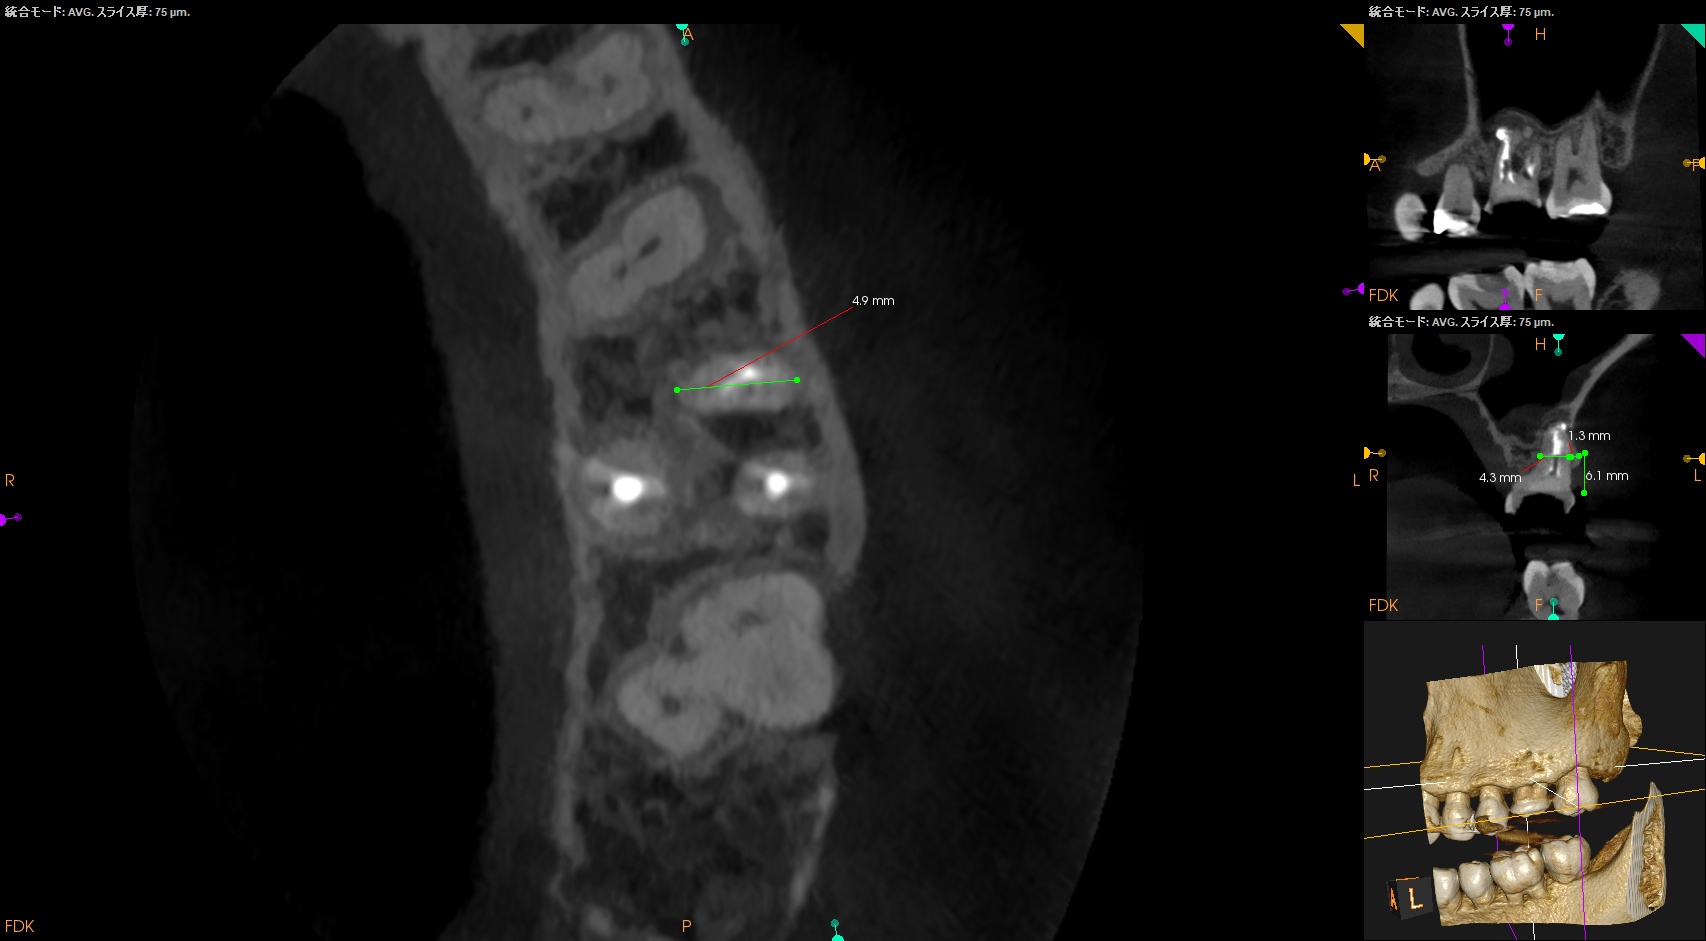

さて、外科の際は

上顎洞の穿孔を避けるため、MBはCEJよりも5.6mm下方に1.3mm Osteotomyして頬舌的に4.3〜4.9mm切断する必要がある。

これはそれほど困難ではない。

その後、Root tipごと取り出す形になるだろう。